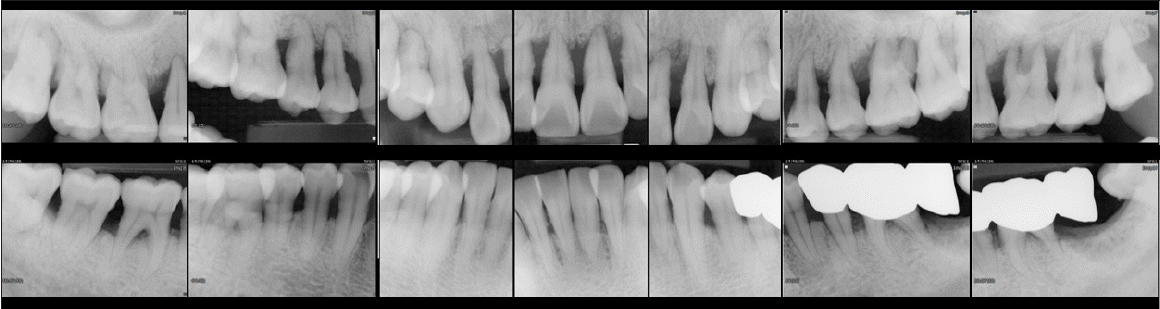

A 44-year-old female first presented in 1988 to the Department of Periodontology at Seoul National University Dental Hospital with generalized gingival discomfort. The patient had undergone orthodontic treatment approximately 30 years earlier but had no other significant dental or medical history.Comprehensive periodontal examination in 1988 revealed generalized Stage III periodontitis, with 33% of sites showing probing depth (PD) ≥4 mm. No teeth had been lost due to periodontitis at that time. Radiographic assessment demonstrated generalized horizontal alveolar bone resorption. Initial non-surgical periodontal therapy included two visits of scaling and root planing with oral hygiene instruction, followed by full-mouth periodontal surgery performed in three appointments with flap elevation and alveolar bone recontouring.After completion of active periodontal treatments, the patient was placed on supportive periodontal therapy and has been maintained for 35 years, attending a total of 169 recall visits. During this period, further interventions were provided as indicated. In 2004, subgingival curettage under local anesthesia was performed. In December 2007, approximately 20 years after the first visit, the maxillary right second molar was extracted due to increased mobility and bite pain. Vertical bone resorption was observed up to the apex. The following year, in 2008, an implant placement with simultaneous sinus floor elevation was performed in the maxillary right second molar region. In 2013, recurrent periodontal deep pockets were treated with full-mouth open-flap debridement, and in 2015, flap surgery was performed again in the left maxillary posterior region. Guided tissue regeneration for intrabony defects was performed at the maxillary left first molar in 2022. The procedure was limited to natural teeth with periodontal pockets ≥6 mm and no mobility. It consisted of applying an inorganic bovine bone mineral (OCS-B®, NIBEC, Jincheon, Korea) and a collagen membrane (Bio-Gide®, Geistlich Pharma AG, Wolhusen, Switzerland) after comprehensive periodontal treatment, followed by suturing.The proportion of sites with PD ≥4 mm decreased progressively over the years: 33% at baseline, 14% in 2004, 12% in 2018, and 9% in 2022 (Fig. 1). All natural teeth were preserved except for the maxillary right second molar. Serial radiographs demonstrated stable periodontal support and function throughout the 35-year follow-up period (Fig. 2).- Case 2

Figure 1.

Full-mouth distribution of probing depth (PD) at four time points: baseline in 1988, and during supportive periodontal therapy at 16 years (2004), 30 years (2018), and 34 years (2022). A progressive reduction in the proportion of sites with PD ≥4 mm was observed over the 35-year maintenance period. Representative full-mouth periapical radiographs of baseline (1988) and the most recent follow-up (2022) are also presented, demonstrating generalized alveolar bone loss at initial examination and stable periodontal support after long-term maintenance.